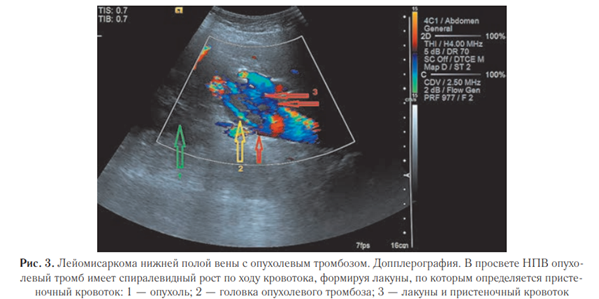

В просвете НПВ опухолевый тромб оттесняет или расслаивает интиму и имеет спиралевидный рост по ходу кровотока, что является важным критерием при дифференциальной диагностике с другими опухолевыми тромбами НПВ, а также с геморрагическим тромбозом.

При спиралевидном росте в просвете НПВ и отслойки интимы могут формироваться лакуны и при частичной или полной обтурации их просвета формируют пристеночные тромботические массы, связанные с нарушением локальной гемодинамики в просвете НПВ, что принципиально важно не только в дифференциальной диагностике, но и во время операции — есть высокий риск отхождения тромботических масс из этих лакун.

При допплерографии хорошо виден пристеночный кровоток через эти лакуны, когда их просвет свободный и не занят тромботическими массами. Формирование этих лакун связано с наличием выраженного коллатерального кровотока за счет поясничных вен и кровотока из почечных вен, если они не сдавлены основным массивом опухоли, а также надпочечниковых и гонадных вен (рис. 3, 4).